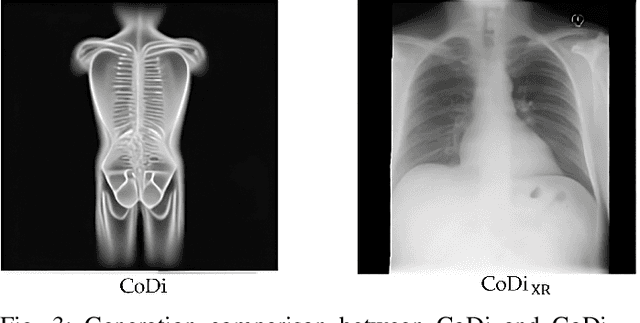

Abstract:Artificial Intelligence is revolutionizing medical practice, enhancing diagnostic accuracy and healthcare delivery. However, its adaptation in medical settings still faces significant challenges, related to data availability and privacy constraints. Synthetic data has emerged as a promising solution to mitigate these issues, addressing data scarcity while preserving privacy. Recently, Latent Diffusion Models have emerged as a powerful tool for generating high-quality synthetic data. Meanwhile, the integration of different modalities has gained interest, emphasizing the need of models capable of handle multimodal medical data.Existing approaches struggle to integrate complementary information and lack the ability to generate modalities simultaneously. To address this challenge, we present MedCoDi-M, a 6.77-billion-parameter model, designed for multimodal medical data generation, that, following Foundation Model paradigm, exploits contrastive learning and large quantity of data to build a shared latent space which capture the relationships between different data modalities. Further, we introduce the Multi-Prompt training technique, which significantly boosts MedCoDi-M's generation under different settings. We extensively validate MedCoDi-M: first we benchmark it against five competitors on the MIMIC-CXR dataset, a state-of-the-art dataset for Chest X-ray and radiological report generation. Secondly, we perform a Visual Turing Test with expert radiologists to assess the realism and clinical relevance of the generated data, ensuring alignment with real-world scenarios. Finally, we assess the utility of MedCoDi-M in addressing key challenges in the medical field, such as anonymization, data scarcity and imbalance learning. The results are promising, demonstrating the applicability of MedCoDi-M in medical contexts. Project page is at https://cosbidev.github.io/MedCoDi-M/.